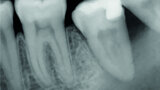

Fig. 9: Post-op periapical radiograph.